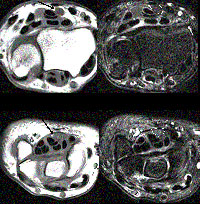

MRI nadgarstka – badanie drogie i mało dostępne, pozwala na wizualizację anatomiczną pola operacyjnego , uzyskanie obrazu nerwu pośrodkowego i wykazanie jego obrzęku. Przydatne zwłaszcza przy podejrzeniu guza nadgarstka. Nie jest rutynowo zalecane w zespole cieśni nadgarstka wg aktualnych zaleceń AAOS (American Academy of Orthopaedic Surgeons, luty 2016)

Rezonans magnetyczny nadgarstka.